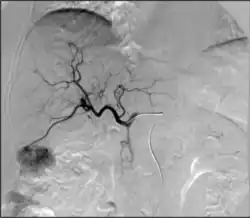

• Kidney cancer: kidney tumors such as renal cell carcinoma can be treated with image-guided ablation (RFA, MWA, cryotherapy) with similar results to partial nephrectomy. Generally, surgery via an either partial or total nephrectomy (removal of kidney) is most often curative but for patients with a smaller lesion or who are not ideal surgical candidates, radiofrequency or cryoablation ablation can be a curative option.[71] Advantages of cryoablation include the ability to visualize the ice ball as well as use more than one probe simultaneously to create the desired ice ball shape. Benign kidney tumors such as angiomyolipomas can be treated with transarterial embolization to shrink the tumor size and reduce the risk of rupture/bleeding. Other embolizations are also performed for symptom relief or prior to surgery to reduce bleeding.[72]